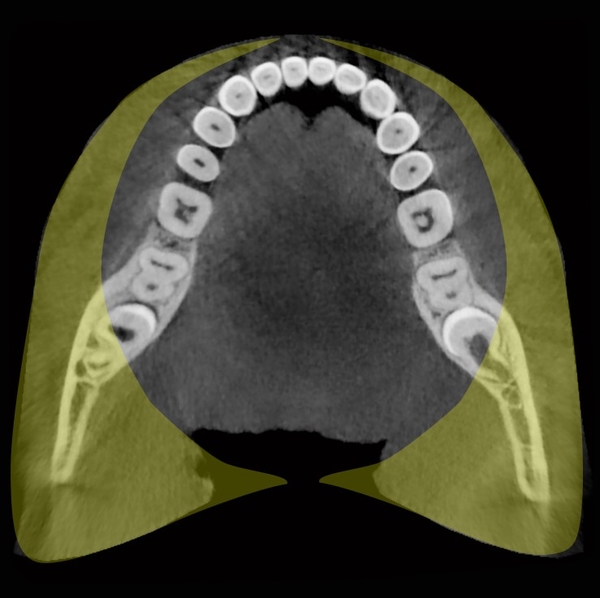

Una buona parte delle CBCT sul mercato offre volumi cilindrici dal diametro di 80 o 90mm. Questi dispositivi sono raramente in grado di acquisire per intero le due arcate dentali, soprattutto nell’area degli ottavi e ancor meno nei casi in cui questi elementi siano malposizionati. Uno studio clinico condotto su un campione di 1020 pazienti ha evidenziato come solo l’1.4% dei pazienti avesse un’anatomia tale da poter essere completamente rappresentata con un volume di dimensione 80x80mm.

Ciò comporta che quasi certamente i pazienti sottoposti a un esame radiografico con un dispositivo con FOV (Field of View – campo visivo) 80x80mm non possano essere completamente indagati, con la conseguente probabilità di dover ripetere l’esame o di dover effettuare ulteriori esposizioni sulle aree mancanti. Anche nel caso di dispositivi con diametro 90mm quasi la metà dei pazienti avrebbe lo stesso problema. Per avere una ragionevole certezza di includere tutti gli elementi anatomici nel nostro esame, dovremmo ricorrere a dispositivi con un diametro di almeno 110mm e una altezza di 85mm.

Aree incluse in un diametro di 80mm e aree escluse (in giallo)